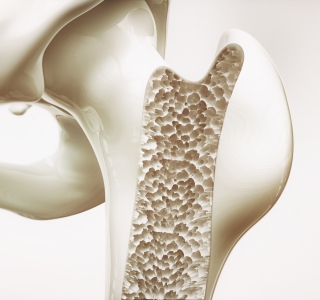

Degenerative Erkrankungen

19.10.2017